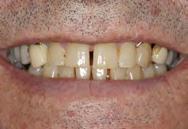

Se presenta una paciente de 52 años de edad, con tratamiento previo inconcluso. Es diagnosticada en el CESO con clase II esquelética, de crecimiento hiperdivergente, biotipo dolicofacial, con clase III canina y molar izquierda, clase III molar derecha, canino 13 retenido, mordida abierta anterior, ausencia de molares 26 y 46.

Se presenta una paciente de 52 años la cual menciona que ya había recibido un tratamiento previo de ortodoncia que quedó inconcluso, actualmente todavía tiene los braquetes de ese tratamiento. Pero ahora ella quiere iniciar un nuevo tratamiento en el CESO con el fin de mejorar su mordida. Es diagnostica con clase II esquelética, de crecimiento hiperdivergente, biotipo dolicofacial, clase III canina y molar izquierda,

Dentista y Paciente 46 Caso clínico

Figura 1. Frente y perfil. Figura 2. Lateral derecha, frente, izquierda de inicio.

clase III molar derecha, canino 13 retenido, mordida abierta, ausencia de los molares 26 y 46.

Estudios de inicio extraorales

En las fotografías de inicio en la de frente (Figura 1) se observa la presencia de los brackets que todavía no han sido retirados y que son del tratamiento anterior, el perfil convexo.

Estudios de inicio intraorales

Las fotografías nos muestran en la Figura 2, la aparatología que se utilizó en el tratamiento que ella no terminó. La mordida abierta anterior de 1.5 mm, en la de frente las líneas medias no coincidentes, la clase III canina y molar izquierda, ausencia del canino 13 y del molar 46; en la Figura 3 el botón de Nance, algunos espacios en las arcadas.